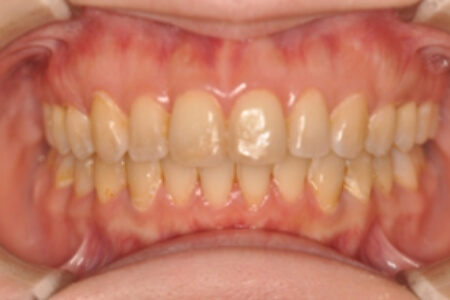

でっ歯(非抜歯)【2104】

初診時

年齢

30歳 性 別 女性

治療期間 2年11か月 費 用 矯正施術料:1,000,000円

調整料:4,000円/月

治療内容の詳細 初診時30歳の女性で、全体的ながたつきを主訴として来院されました。

検査の結果、過蓋咬合を伴う、アングルⅡ級1類不正咬合と診断しました。

治療としては、非抜歯の上、セルフライゲーションブラケット装置(デーモンシステム)とマウスピース矯正装置(インビザライン)で歯の配列を行いました。

同時に顎間ゴムにて咬合関係の改善を行いました。

治療期間は2年11か月でした。